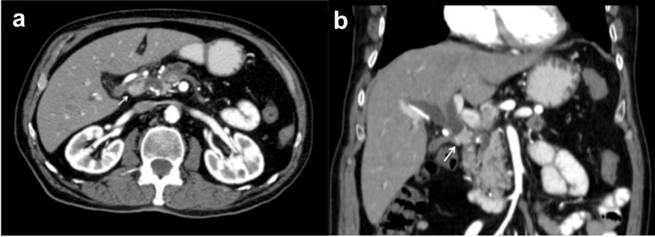

Computed tomography revealed intrahepatic and extrahepatic bile ducts dilatation (Figure 1). Distal to the bifurcation an intraluminal mass measuring 1.9x1.2 cm was noticed obstructing the bile duct. Dilation of the main pancreatic duct in the body and tail of the pancreas was also noticed. No vascular involvement was found. An endoscopic retrograde cholangiographic (ERCP) examination was elected due to the growing levels of bilirubin and operating room availability. The exam revealed complete obstruction of the common bile duct and a stent was introduced. The patient underwent surgical exploration for suspicion of cholangiocarcinoma. A tumor of the common bile duct was found at surgery. A careful dissection of the extrahepatic bile duct was carried out along with lymph node of the hepatoduodenal ligament. The bile duct at the level of the bifurcation was transected and the proximal edge sent for pathology examination. The dissection was carried to the level of the pancreas and the distal edge of the duct sent for pathology as well. Frozen section from the distal margin revealed atypical cells in the mucosal leaning of the bile duct. The biopsy from the hepatic duct bifurcation revealed normal cells. Due to these findings we have opted to continue with a Whipple operation. Operative and post-operative course was uneventful. Microscopically the tumor of the common bile duct was a mixed poorly differentiated adenoneuroendocrine carcinoma. The tumor showed invasion to the fat tissue, lymphatic vessels and nerves (Figure 2a). Immunohistochemical analysis showed neoplastic cells diffusely positive for chromogranin A, synaptophysin and C56 (Figure 2b). No lymph node metastases were found in the fatty tissue surrounding the bile duct. Multiple foci of moderately differentiated adenocarcinoma were found in the head of the pancreas at microscopic examination of the pancreas. Two out of nine lymph nodes adjacent to the pancreas showed metastases. One bearing neuroendocrine carcinoma metastasis, and the other metastasis of adenocarcinoma. All other lymph nodes in the specimen were negative for tumor cells.

Figure 1. CT scan showing a lesion within the common bile duct (a.) resulting in proximal bile duct dilatation (b.). |